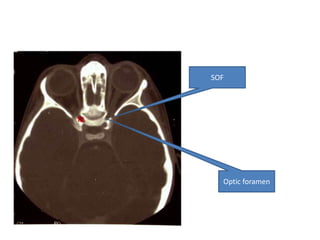

SOF Opticforamen

SOF

Optic foramen

Orbit